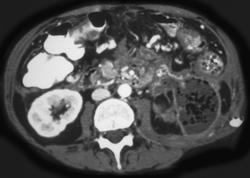

问题 女性,34岁,寒战、高热、急性中上腹偏左腹痛,压痛,CT扫描如图,最可能的诊断是 ( )

选项 A、胰腺癌 B、胰腺转移癌 C、胰腺脓肿 D、慢性胰腺炎急性发作 E、急性胰腺炎

答案 C